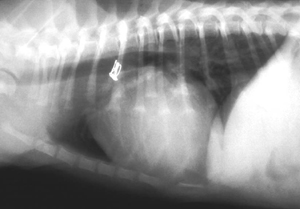

Radiograph after coil closure of PDA

Angiography after successful coil closure:

Post-procedure angiography showing no relevant residual flow through the ductus after closure.